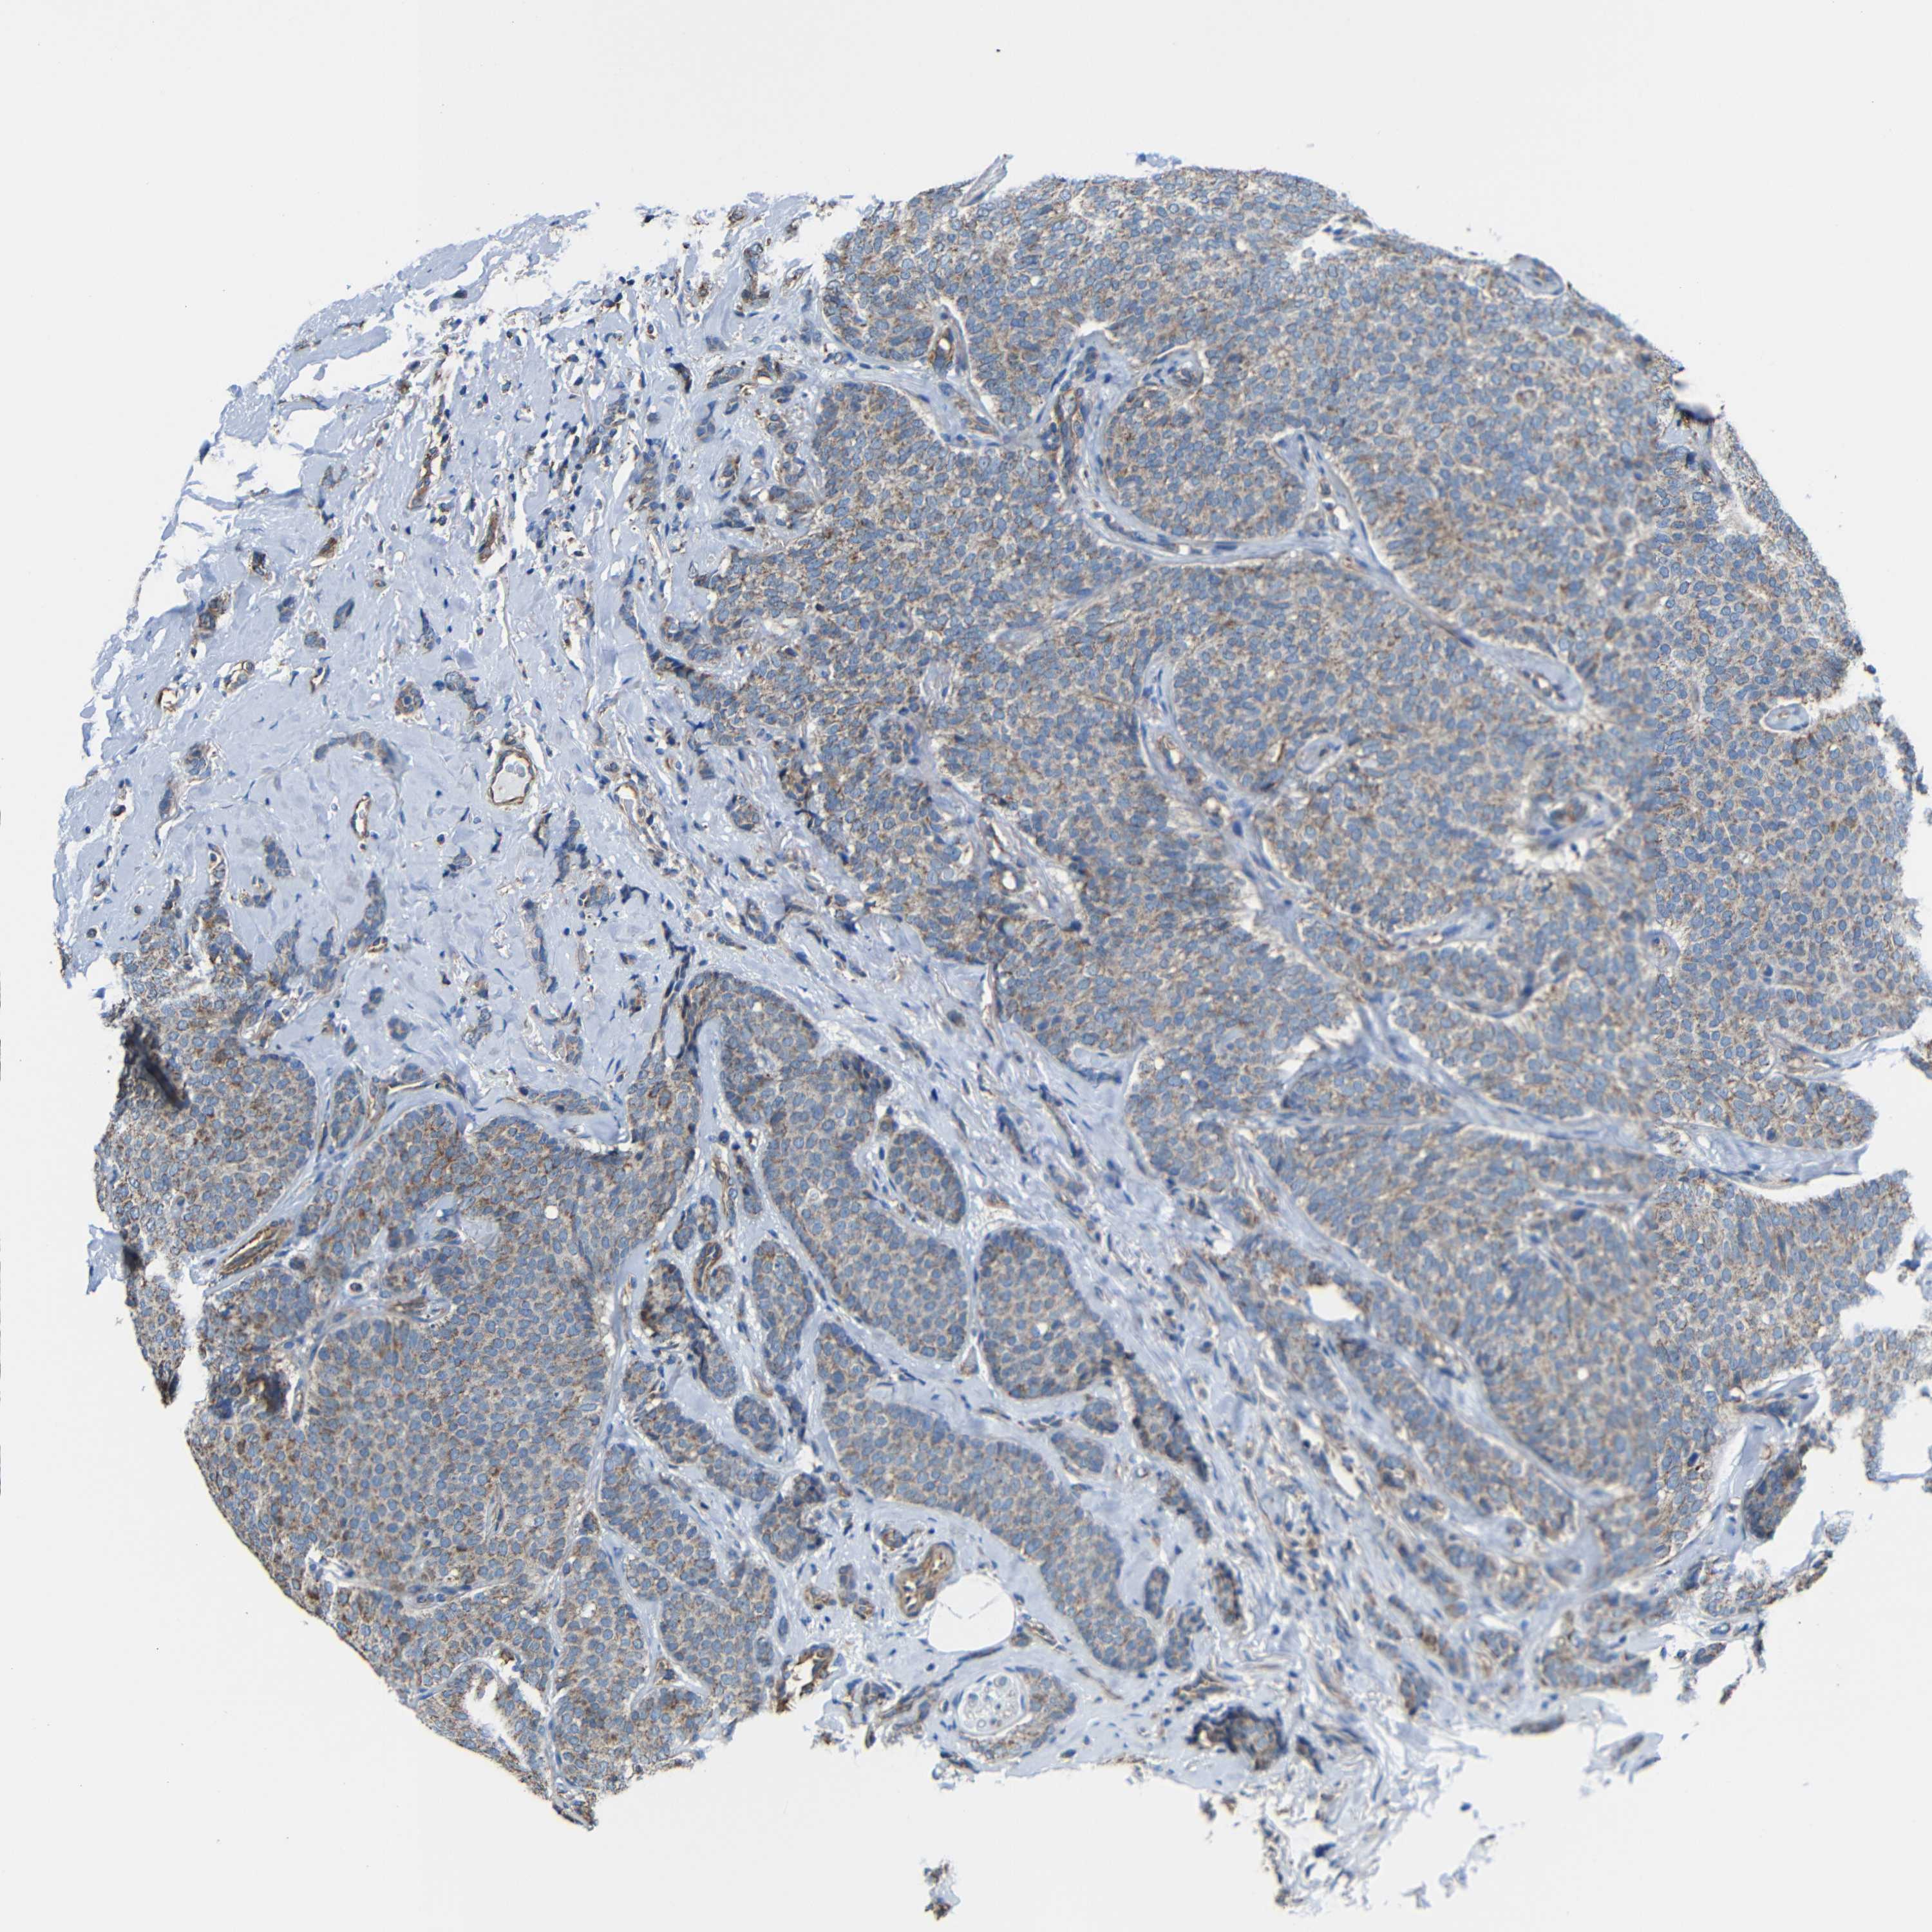

CANCER BREAST CANCER Show tissue menu

BRCA TCGA BRCA VALIDATION PROTEIN EXPRESSION